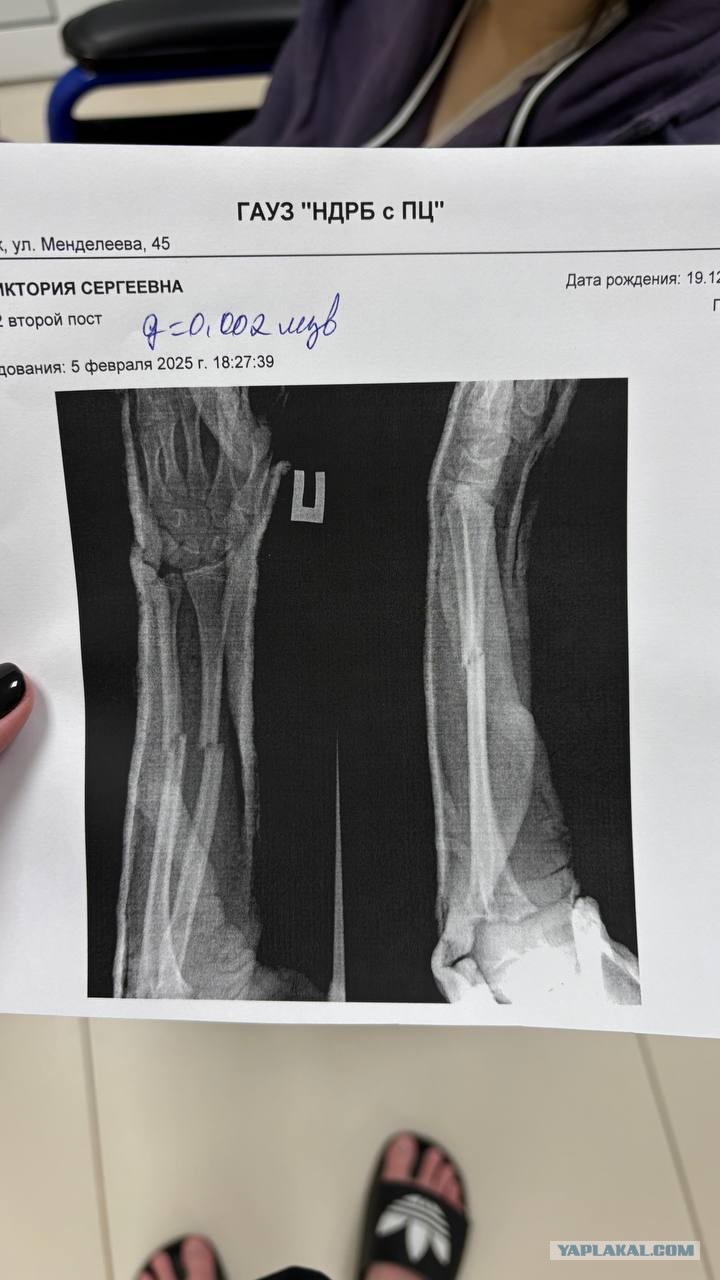

И так она сломалась

И так она сломалась 111 фото